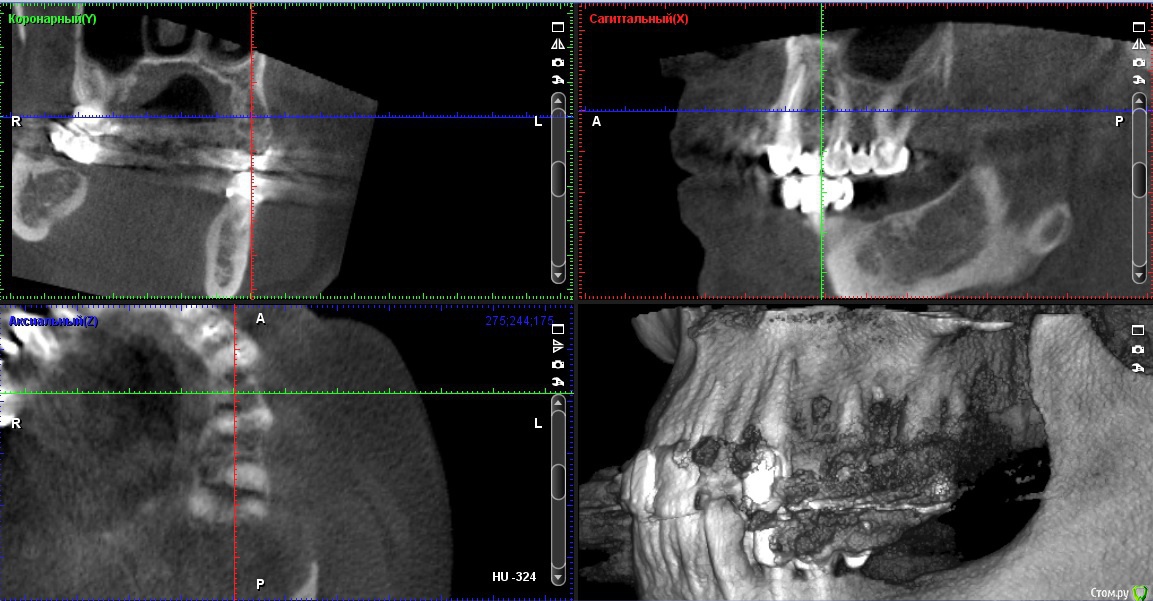

Мк стоят около 10 лет,в области 23 средней 1/3 определяется свищ,отделяемого нет,небольшое западение альвеолярного отростка с рубцовыми изменениями слизистой в области 24 ,перкуссия 23,25 безболезненна,болезненность в области переходной складки и небной поверхности на уровне апекса 23

Со слов пациента периодически возникающий отек,тянущие боли

Около недели назад был похожий случай: пациент мост 1.6-1.4. В промежутке неясного генеза убыль кости по снимку. Делаем КТ - очаг просветления в области отсутсвующего зуба, по снимку  вроде кость 4 типа. Объясняю пациенту, что будем ставить имплантат, раскроемся и увидим что там. День Х, после отслоения в области удаленного зуба 1.5 грануляционная ткань! 30 минут кюретажа всех этих спаек и получена практически первоначальная лунка удаленного зуба 1.5. Закинул кость и вкрутил имплантат. Ушил, а на момент когда пациент вышел из кресла - сказал, что сало прям легче. мол было даже желание вам доктор помочь все это из лунки убрать))) 2 недели все гуд - ничего не беспокоит. Так вот к чему так много букав: скорее всего удалили зуб и не сделали кюретаж, там грануляционная ткань которая дает всю эту картину. Побольше бы срезов с КТ. И сделайте сагитальные срезы. Если полость из неоткуда то режьте и смотрите.